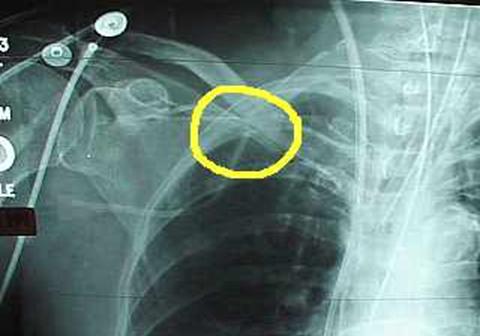

• Pinch-off syndrome